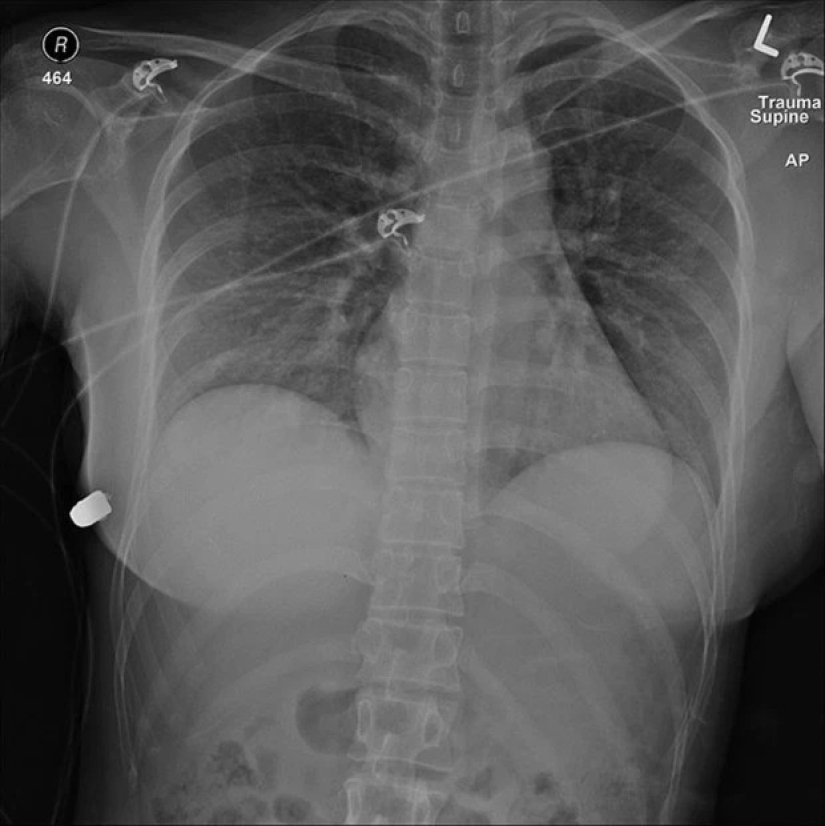

The 40-year-old model's car crashed into a tree at high speed while she was driving home at night. The woman's whole life flashed before her eyes. The impressive implants softened the blow and saved Sheila's life. The beauty's chest was damaged, but the rest of her body remained intact.